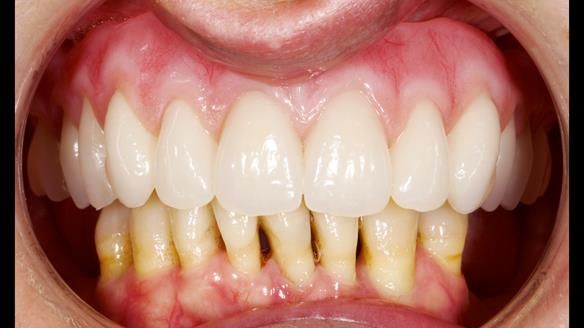

She had previously suffered from generalised periodontitis – stage IV, grade C, currently stable, with reduced attachment across the upper arch.

By the time she came to me, her periodontal condition was stable — but the aesthetics in the upper jaw were very poor.

We provided her with an immediate upper denture (Mk 1), followed by a definitive metal-based upper denture (Mk 2). A lower removable partial denture was discussed, to be made only if needed once the upper treatment was complete. However, at review, this wasn’t necessary — Adnana had excellent neuromuscular control and function, even with a shortened dental arch (SDA).

- Definitive denture (Mk 2), metal-based and custom-designed for her face

- A restored smile, restored lip support, and a patient who owned the journey